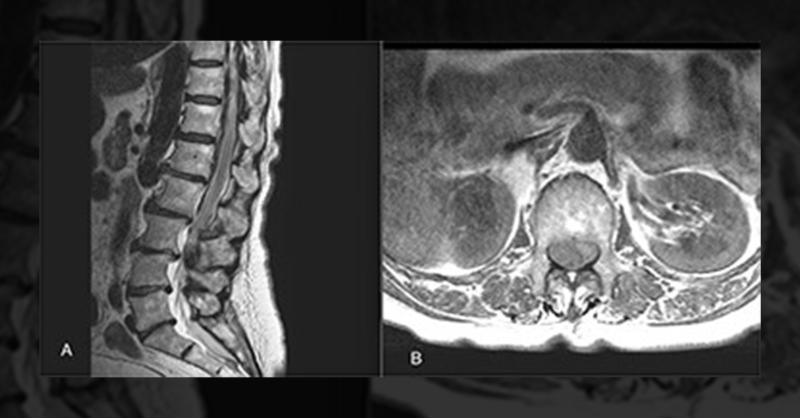

- Spinal Hematoma as a Complication of Anaesthesia

A 77-year-old woman was admitted for a total knee arthroplasty (TKA) on her right knee. Her medical history included an ischemic stroke in 2019 with no residual effects and hypertension. Her preoperative assessment, including coagulation profile and platelet count, was normal. Physical examination prior to surgery revealed normal strength and funct

Spinal Hematoma as a Complication of Anaesthesia